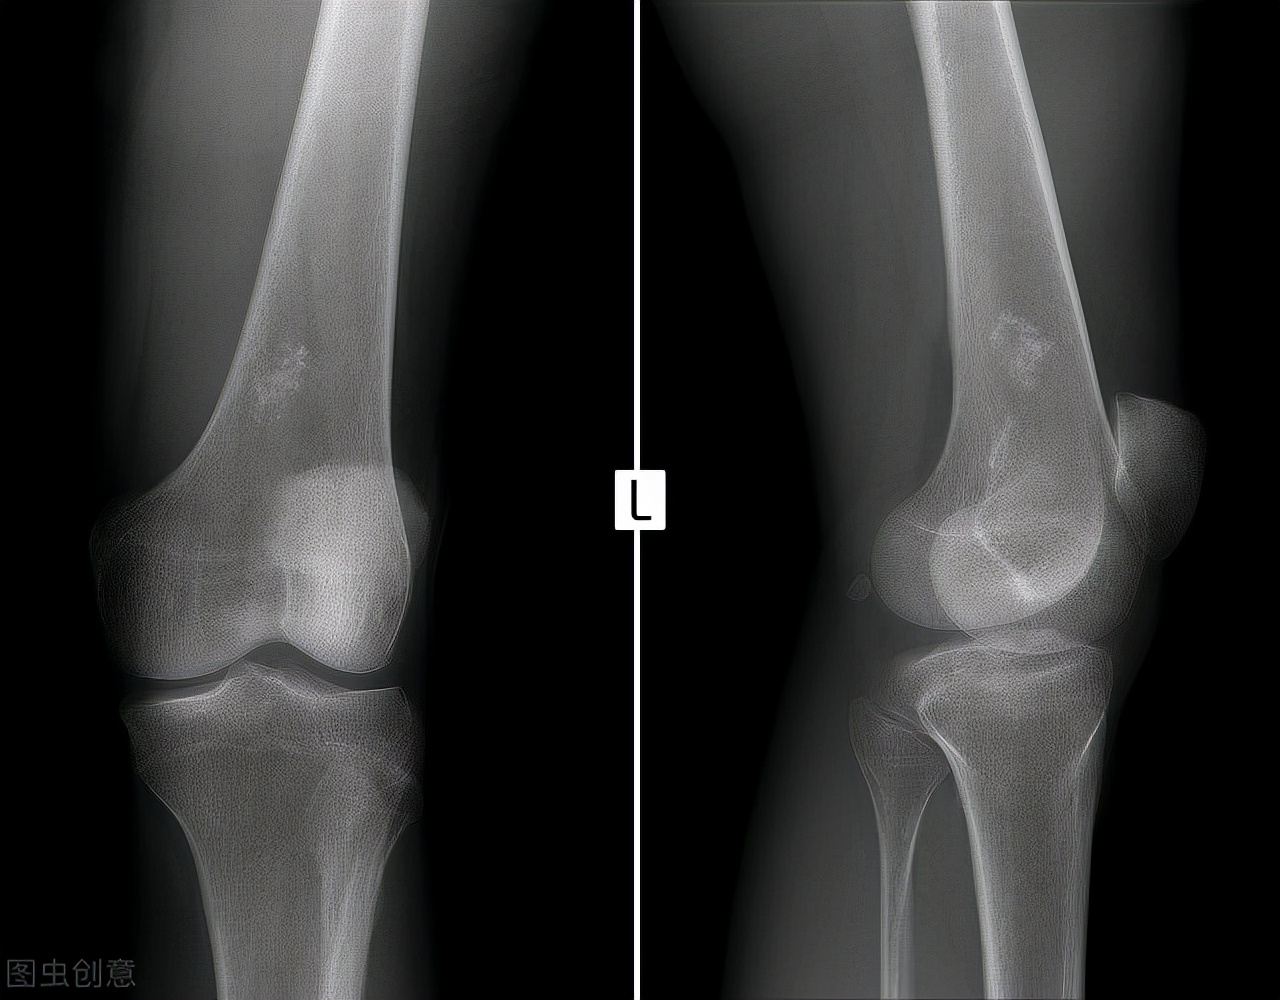

首先,我们看看,老年人群腰背部酸痛最常见的疾病有哪些?发病率最高,目前最常见的要数腰椎间盘突出了,尤其是经常过度弯腰工作的人群,该类人群经常使腰部处于负重的状态,在加上腰椎间盘发生老化,容易使髓核突出,所以发生腰椎间盘突出以后容易腰酸、腰痛。除此之外,因为人体的神经走行在椎管之中,腰椎间盘突出以后,容易挤压椎管之中的神经,患者会同时出现腿部的疼痛,严重时甚至会有手足麻木,有时患者的日常生活也会受到影响,行走时可能会出现跛行。那么,除了腰椎间盘突出以外,那些人群还以出现腰酸、腰痛呢?工作时的不良体位、劳动姿势、搬运重物等引起的慢性累积性损伤,遇到潮湿寒冷等物理刺激后极容易发生腰酸、腰痛。转到腰椎间盘突出这个问题,感觉自己腰酸、背痛、手足麻木时,怎么确定自己得了这个病呢?去相应的骨科门诊或脊柱外科门诊,医生给你通过查体,开(MRI),就可以确定是不是了。

综上所述,无论是哪种疾病引起的腰酸、背痛,都需要引起我们的重视,当症状出现时要及时去医院检查,不要自己主观臆断。得到确诊后再依据临床医生的要求行针对性措施。对于骨科疾病,可以做MRI、CT等检查。对于肾脏疾病,可以做尿常规,肾脏B超等检查。对于血液疾病,可以做骨髓穿刺、血常规、蛋白免疫电泳等检查。如果腰酸、腰痛是由肾脏病所引发的,则更需要及时采取措施。这时,腰酸、腰痛就成为肾脏病发生的早期信号,需要引起肾脏病患者的足够重视。肾脏病早期的防治是一个非常关键的环节,不容错过。